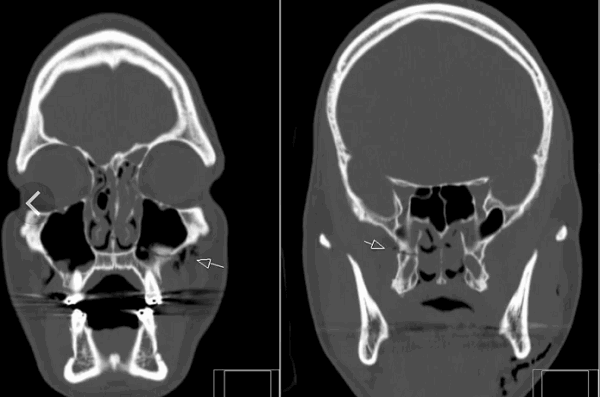

Кости черепа.

По МРТ можно определить перелом костей черепа. Кости свода плоские, видны на МРТ как темная тонкая полоска между кожей и мозговыми оболочками. При обследовании в разных проекциях можно обнаружить линии перелома. Однако они хорошо заметны и при обычной рентгенограмме. Она стоит дешевле и делается быстрее. Зато она не показывает, что происходит с мозгом и оболочками в результате травмы головы. На снимках МРТ можно определить, повреждены ли кроме костей мягкие структуры, есть ли гематомы, разрывы сосудов, очаги некроза, ушиб мозга. При травмах, которые сопровождаются неврологической симптоматикой, методом уточнения состояния головного мозга после перелома станет МРТ.

Перелом основания черепа, височных костей – всегда сложная травма. Она затрагивает множество структур, проходящих между костями, их отростками, внутри полостей. Наиболее полную картину после травмы черепа можно получить именно благодаря томографии на основе магнитного резонанса.